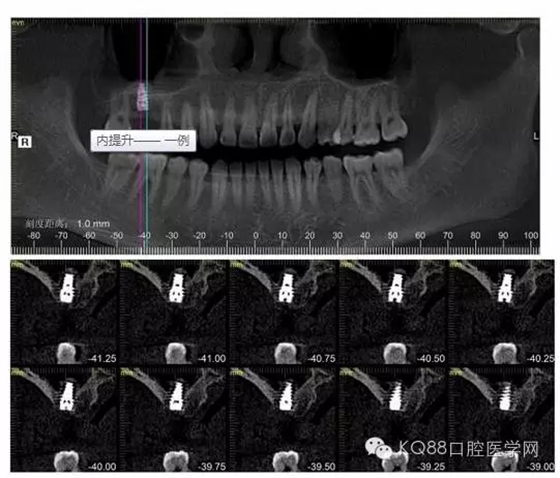

植入后,CBCT

另外一個(gè)切面。竇底粘膜完整連續(xù)。可以看到上下咬合的位置關(guān)系。

下面兩張是種植前后的對(duì)比片子。

手術(shù)前

手術(shù)后。